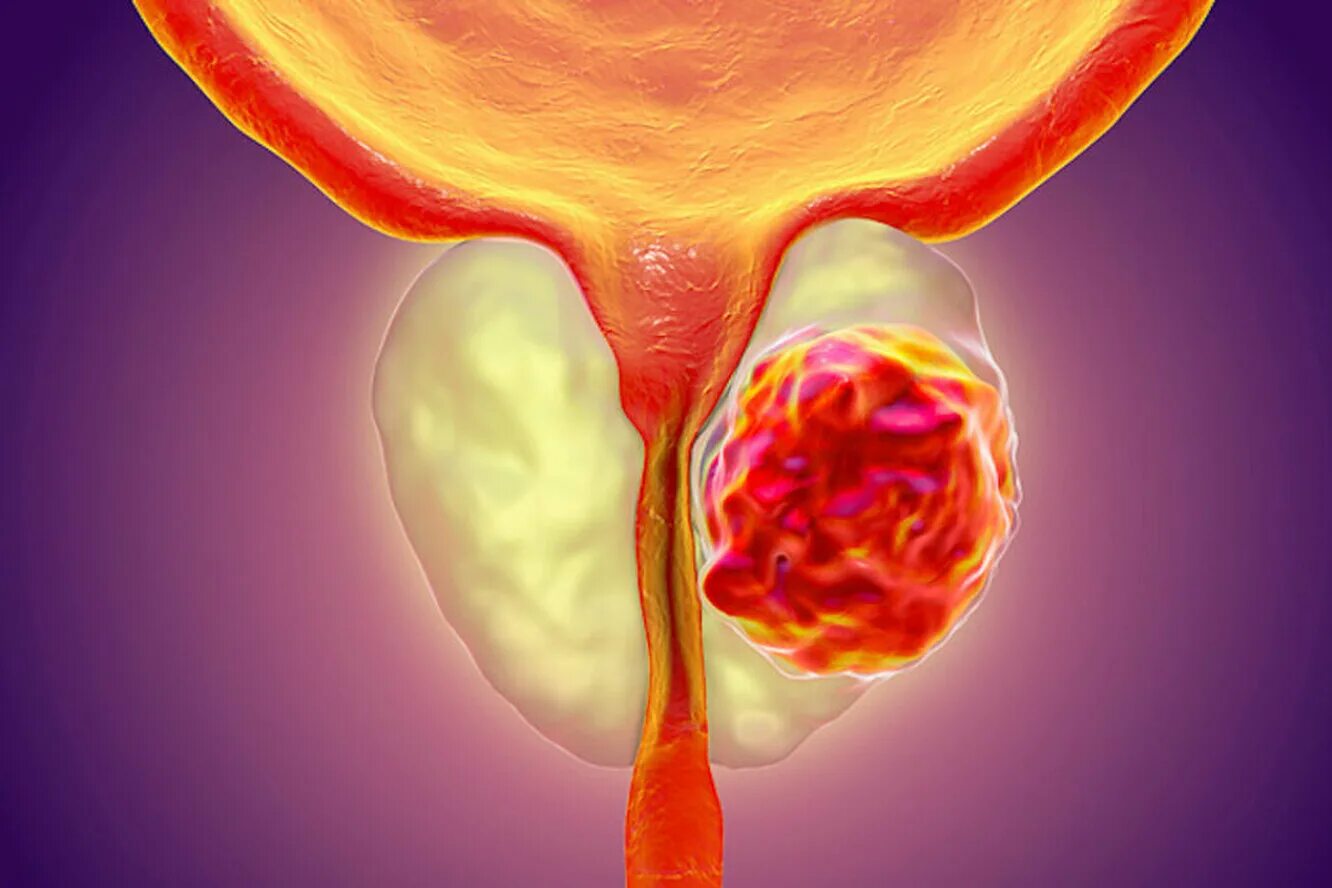

Опухоль предстательной железы. Карцинома предстательной железы. Опухоль предстательной железы презентация. Онкология предстательной железы

Опухоль предстательной железы. Карцинома предстательной железы. Опухоль предстательной железы презентация. Онкология предстательной железы Опухоль предстательной железы. Злокачественная опухоль предстательной железы. Карцинома предстательной железы. Предстательная железа развивается из

Опухоль предстательной железы. Злокачественная опухоль предстательной железы. Карцинома предстательной железы. Предстательная железа развивается из Новообразование предстательной железы. Отек предстательной железы. Заболевания предстательной железы презентация. Опухоль предстательной железы презентация

Карцинома предстательной железы. Аденома простаты злокачественная. Злокачественная гиперплазия простаты. Аденома простаты онкология Опухоль предстательной железы. Карцинома предстательной железы. Злокачественное новообразование предстательной железы. Объемное образование предстательной железы

Опухоль предстательной железы. Карцинома предстательной железы. Злокачественное новообразование предстательной железы. Объемное образование предстательной железы Предстательная железа 3д. Опухоль предстательной железы. Злокачественные новообразования простаты. Карцинома предстательной железы

Предстательная железа 3д. Опухоль предстательной железы. Злокачественные новообразования простаты. Карцинома предстательной железы Карцинома предстательной железы. Что такое РПЖ предстательной железы. Онкология предстательной железы. Злокачественное новообразование предстательной железы

Опухоль предстательной железы. Злокачественное новообразование предстательной железы. Карцинома предстательной железы. Tumor предстательной железы Опухоль предстательной железы. Онкология предстательной железы. Узлы в предстательной железе. Злокачественная опухоль предстательной железы

Опухоль предстательной железы. Онкология предстательной железы. Узлы в предстательной железе. Злокачественная опухоль предстательной железы Злокачественная опухоль предстательной железы. Злокачественные новообразования простаты. Карцинома предстательной железы. Стадии опухоли простаты